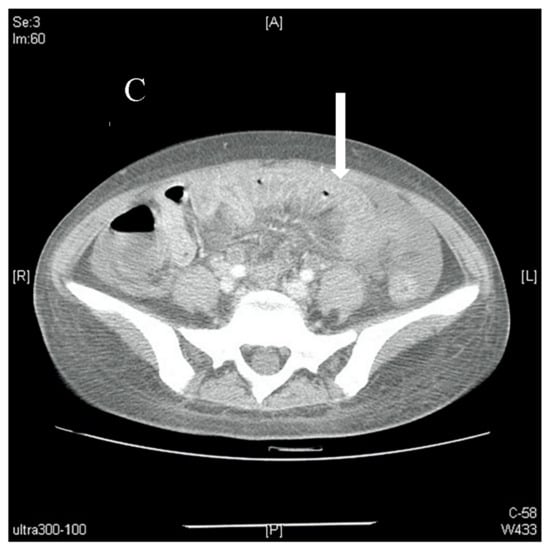

Further blood investigations revealed hypoalbuminaemia (2.86 g/dL), with normal coagulation profile, amylase, lipase, and B-type natriuretic peptide. An abdominal computed tomography (CT) scan was performed which demonstrated extensive small bowel wall thickening with enhancement (target sign), and engorgement of visible mesenteric vessels (comb sign) with significant ascites; there were no ischaemic changes nor thrombosis of the mesenteric vessels (Figure 2). No free air suggestive of viscus perforation was seen. Paracentesis was subsequently performed to obtain ascitic fluid for analysis, with the following results: total protein 5.2 g/dL, albumin 2.36 g/dL, and negative bacteriology studies (Gram stain, acid-fast bacilli smear, Mycobacterium tuberculosis culture). Serum-ascites albumin gradient (SAAG) was 0.5 g/dL, prompting further investigation into peritoneal causes of the patient’s ascites.

Figure 2.

(A). Axial view of a contrast-enhanced abdominal CT scan showing massive ascites (arrow) with no signs of occlusion or filling defect in major vessels. (B). Axial view of a contrast-enhanced abdominal CT scan showing bowel-wall thickening and enhancement, which is also known as target sign (arrow). (C). Axial view of a contrast-enhanced abdominal CT scan showing edematous ileum wall with engorgement of mesenteric vessels and increased number of visible vessels, which is also known as comb sign (arrow).

Comb sign was found on CT imaging of our patient’s abdomen. This sign refers to the hypervascular mesenteric appearance, usually seen in acute inflammatory conditions of the bowel and mesentery. In hindsight, the presence of comb sign in our patient’s abdominal CT scans is indicative of LMV [7]. Imaging, in particular CT scans, is the main modality for diagnosing LMV [8,9].